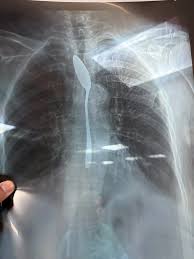

استقبل قسم الطوارئ بمستشفى شبين الكوم التعليمي حالة سيدة تبلغ 77 عامًا من مركز تلا، بعدما ابتلعت معلقة شاي في محاولة انتحار، وتعاني من اكتئاب ممتد منذ خمس سنوات.

قاد الفريق الطبي، بقيادة الدكتور أحمد نبيل شهاب، الفحص السريع وإجراء الأشعة اللازمة، ثم نجح في استخراج المعلقة باستخدام منظار طبي دون أي مضاعفات، مع متابعة دقيقة للحالة.